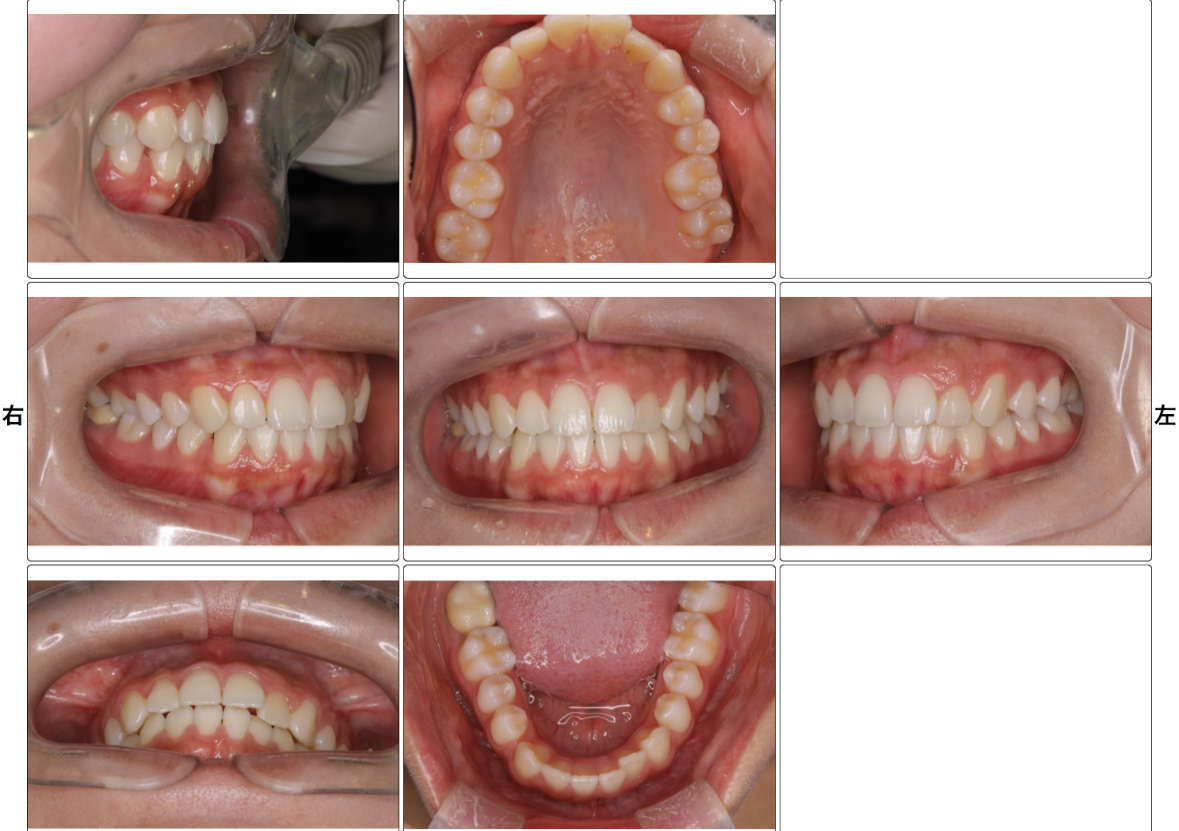

3. 口腔内写真撮影(16枚撮影):5分

「口腔内写真(お口の中の写真)」「お顔の写真」を数枚撮影します。

治療前の状態を記録しておくことで、今後の治療計画や経過観察にも役立ちます。

口腔内写真撮影